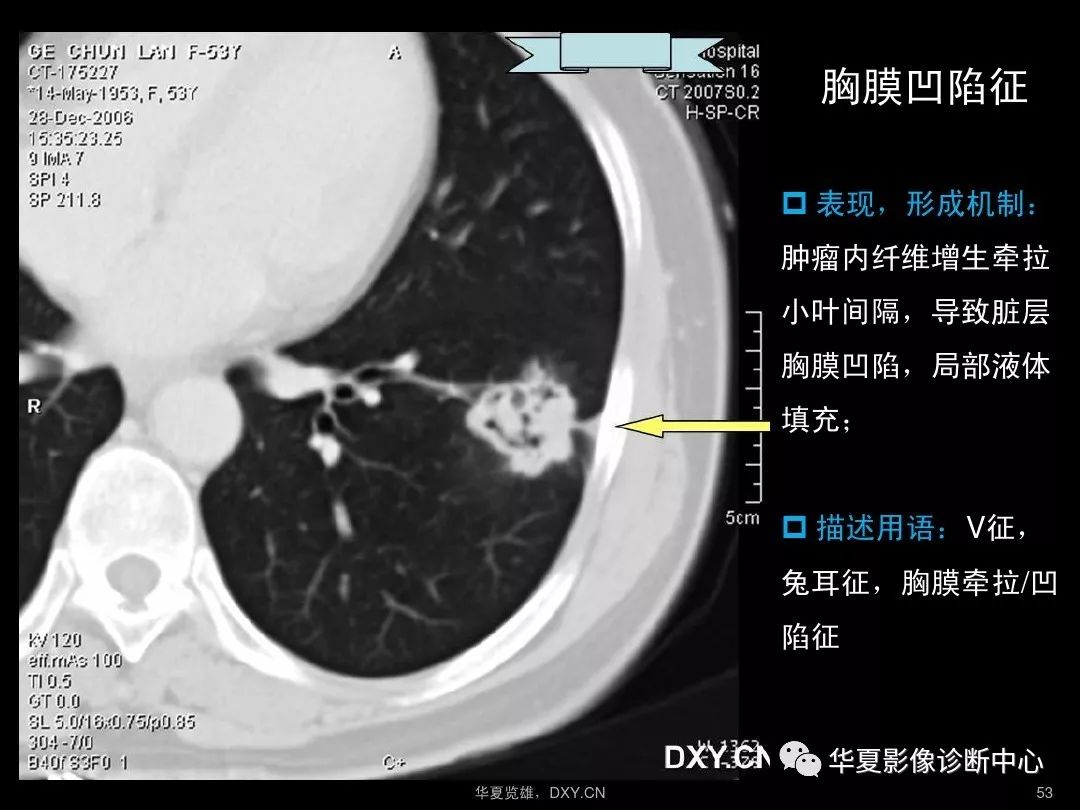

胸部ct读片技巧汇总 - 知乎

临床医生胸部ct读片扫盲知识ppt